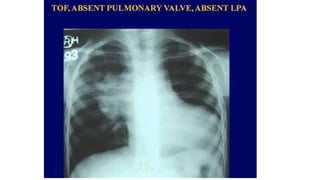

Tetralogy of Fallot

BOOT SHAPED SIGN

Tetralogy ofFallot

• 10%–11% of cases of congenital heart disease

• As a result of single defect, an anterior malalignment of the

conal septum

• Components:

• Ventricular septal defect

• Infundibular pulmonary stenosis

• Overriding aorta

• Right ventricular hypertrophy.

• Heart has the shape of a wooden shoe or boot

• Blood flow to the lungs is usually reduced

Tetralogy ofFallot • 10%–11%of cases of congenital heart disease • As a result of single defect, an anterior malalignment of the conal septum • Components: • Ventricular septal defect • Infundibular pulmonary stenosis • Overriding aorta • Right ventricular hypertrophy. • Heart has the shape of a wooden shoe or boot • Blood flow to the lungs is usually reduced